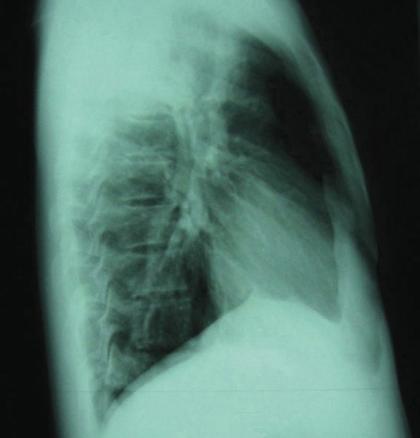

©La Revue du Praticien Radiographie de thorax de profil. Condensation alvéolaire du lobe supérieur droit due à une pneumonie à pneumocoque.